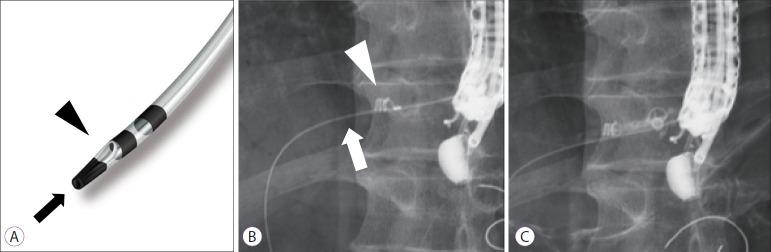

Endoscopic ultrasound (EUS)-guided hepaticogastrostomy (HGS) is widely performed not only as an alternative to transpapillary biliary drainage, but also as primary drainage for malignant biliary obstruction. For anatomical reasons, this technique carries an unavoidable risk of mispuncturing intrahepatic vessels. We report a technique for troubleshooting EUS-guided portal vein coiling to prevent bleeding from the intrahepatic portal vein after mispuncture during interventional EUS. EUS-HGS was planned for a 59-year-old male patient with unresectable pancreatic cancer. The dilated bile duct (lumen diameter, 2.8 mm) was punctured with a 19-gauge needle, and a guidewire was inserted. After bougie dilation, the guidewire was found to be inside the intrahepatic portal vein. Embolizing coils were placed to prevent bleeding. Embolization coils were successfully inserted under stabilization of the catheter using a double-lumen cannula with a guidewire. Following these procedures, the patient was asymptomatic. Computed tomography performed the next day revealed no complications.

摘要

内镜超声(EUS)引导下肝胃吻合术(HGS)不仅作为经乳头胆管引流的替代方法被广泛应用,还作为恶性胆管梗阻的主要引流手段。由于解剖学原因,该技术存在不可避免的误穿肝内血管的风险。我们报告一种用于解决EUS引导下门静脉盘绕的技术,以防止介入性EUS过程中误穿后肝内门静脉出血。计划对一名59岁不可切除胰腺癌男性患者行EUS-HGS。用19号针穿刺扩张的胆管(管腔直径2.8mm),并插入导丝。探条扩张后,发现导丝位于肝内门静脉内。放置栓塞线圈以防止出血。使用带导丝的双腔套管在导管稳定的情况下成功插入栓塞线圈。经过这些操作,患者无症状。次日进行的计算机断层扫描显示无并发症。